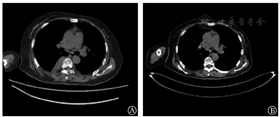

例1鼠源BCMA CAR-T细胞治疗后3个月血尿免疫固定电泳阴性,骨髓活检示骨髓瘤细胞比例降至0,疗效评估为CR。16个月后临床复发,M蛋白定量为11.2 g/L,予以Rd(来那度胺+地塞米松)方案治疗8个月复查M蛋白定量22.7 g/L,骨髓瘤细胞占10%,HGB 72 g/L,胸部CT示胸椎5~10水平右侧椎旁软组织肿块(图1A),考虑病情进展,且出现髓外病变(EMD)。患者入组人源化BCMA CAR-T临床试验(ChiCTR2000033925)。接受FC方案预处理后输注CAR-T细胞2×106/kg,输注后4个月胸CT示髓外病变示胸5-10水平右侧椎旁软组织肿块消失(图1B),骨髓活检示骨髓瘤细胞降至0,M蛋白定量为6.7 g/L,疗效评估为PR。